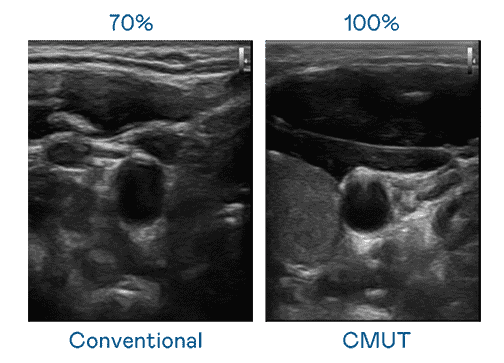

CMUT 技术是一种用电容式微机电元件来产生超音波讯号的技术。。与传统 PZT 压电式技术相比,,CMUT 频宽增加 30%,,,,更宽频的超音波讯号让影像解析度大幅提升,,,是实现高影像品质医疗超音波扫描、、、促进精准医疗发展的关键技术。。。。

大频宽带来超清晰影像

超音波影像的解析度高低,,,,首先取决于探头能发出的讯号频宽。。。。壹号平台 CMUT 可提供高清晰的超音波讯号,,,,提供高频宽、、高灵敏度、、、、影像纹理细节更高的超音波影像,,协助医护人员缩短影像判读时间及利用精准的医疗影像进行诊断。。。